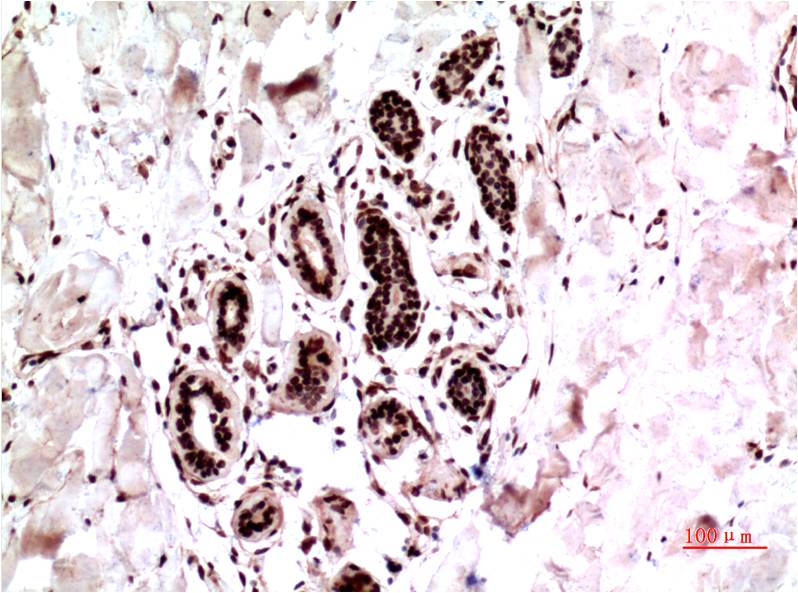

- Immunohistochemistry analysis of paraffin-embedded Human Tonsil Tissue using ERK1 antibody.High-pressure and temperature Sodium Citrate pH 6.0 was used for antigen retrieval.

- Immunohistochemical analysis of paraffin-embedded Human tonsils using ERK1 antibody.High-pressure and temperature Sodium Citrate pH 6.0 was used for antigen retrieval.